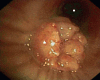

Figure 5

Bronchoscopy. The star indicates a round mass totally obstructing the left lower lobe bronchus and the dot indicates the left upper lobe bronchus.